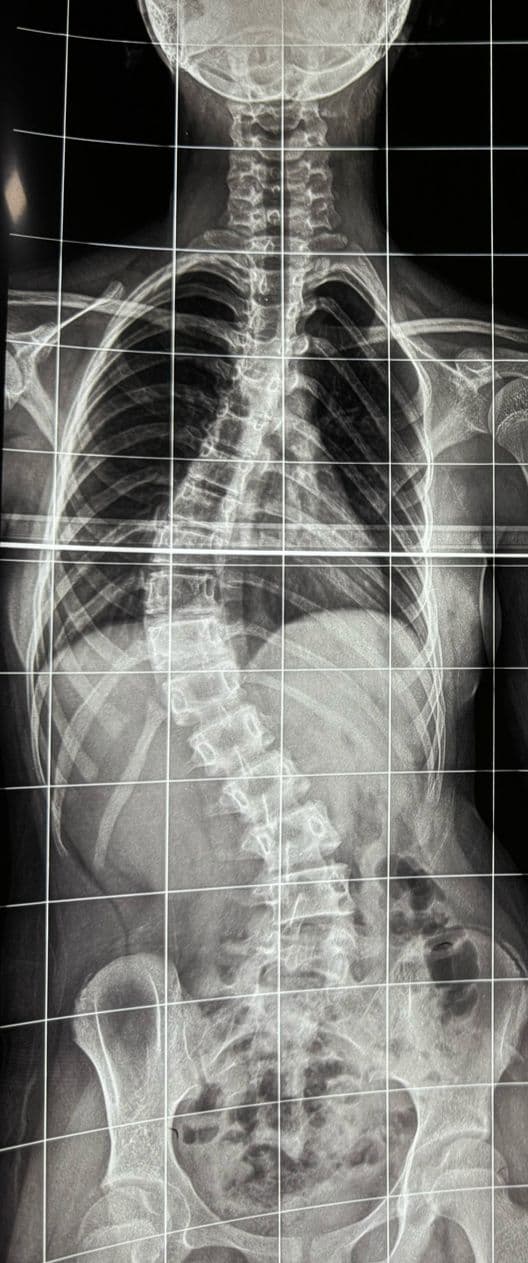

Radiological evaluation with standing spinal X-rays confirmed the presence of a marked, progressive curvature involving both the thoracic and lumbar regions. The degree of deformity was substantial, and if left untreated, it carried a high risk of further progression during growth, potentially resulting in worsening back pain, impaired spinal balance, and even respiratory compromise due to reduced lung capacity. The possibility of long-term disability and restrictions in her quality of life made timely intervention crucial in her management.